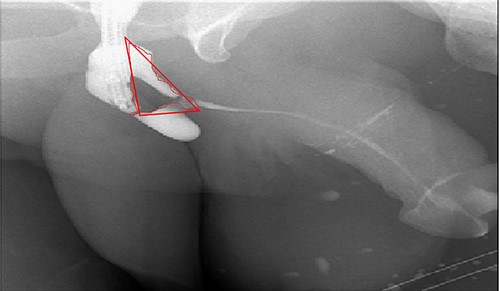

A 38-year-old male was referred to our tertiary hospital due to recurrent urethral stricture for further evaluation and management. His history revealed multiple failed attempts of DVIU, anastomotic urethroplasty and urethroplasty with pedicled fasciocutaneous flap in 2019. Nine months after his surgery, he had complete retention due to stricture recurrence and he underwent multiple dilatations and DVIU but his stricture keep recurring. He was referred to us for definitive management. He was on a suprapubic catheter. Initial workup included retrograde, antegrade cystoscopy and urethrogram. First, an antegrade cystoscope was introduced. The bladder neck, internal sphincter and verumontanum were identified. However, there was no external sphincter due to damage from the previous procedures. A pinpoint opening in the dorsal area of the urethra was seen about 1-cm distal to the verumontanum (Fig. 1, lumen A). Also, a blind-ended urethra in the ventral area was identified (Fig. 2, lumen B). It is most likely from the previous flap. Additionally, the retrograde urethrogram showed that the contrast was only going from the pinpoint hole in the dorsal side of the urethra Fig. 3. Retrograde cystoscopy also showed a blind-ended in the proximal bulbar urethra. We could not identify the small hole that we saw from the antegrade cystoscopy. After initial workup, he was counseled in the clinic for dorsal only buccal mucosal graft (BMG) urethroplasty for which he agreed.

(lumen A): A pinpoint opening in the dorsal area of the urethra as pointed in the arrow.

In the beginning, an inverted Y midline perineal skin incision was made extending from the base of the scrotum to just above the anus. There was an extensive adhesion reaching up to the Colle’s fascia and they were incised. Then, a cystoscope was introduced through the suprapubic channels and a guidewire was inserted through the pinpoint stricture. An 18-French Red Rubber Catheter was advanced per urethral meatus to the stricture. The urethra was dissected from the corpora cavernosa and rotated. After that, the urethra was incised dorsally over the distal tip of the catheter to open lumen A over the previously inserted guidewire (Fig. 1, lumen A). Once lumen A was completely open, the other channel was ventral to the scarred urethral plate. Therefore, the decision was to completely excise this channel to leave the ventral service lined by the previously placed fasciocautonous flap. The resected area is marked by red line in Fig. 4. Then, refashioning the proximal part and distal flap to form the ventral covering of the urethra. After that, harvesting the BMG was done. The harvested BMG was tailored and placed dorsally where it was split-fixed to the corporal body. The proximal and distal apical edges of the graft were sutured to the corresponding dorsal wall of the corpus spongiosum using an interrupted full-thickness 5–0 PDS. After that, the lateral edge of the corpus spongiosum was secured to the lateral aspect of the graft and the underlying tunica albuginea of the corpora using a 5–0 PDS suture on each side allowing the flap to rotate to its original position. Before completion, a 16-French urethral catheter was advanced easily into the bladder. Subcutaneous tissues that included a part of the bulbous spongiosum muscle and Colle’s fascia were closed in a continuous fashion using 3–0 Vicrl. Finally, the skin was closed using 4–0 Vicry-Rapide. The postoperative course was uneventful. Four days later, he was discharged home in a healthy condition. The patient recovered from surgery.